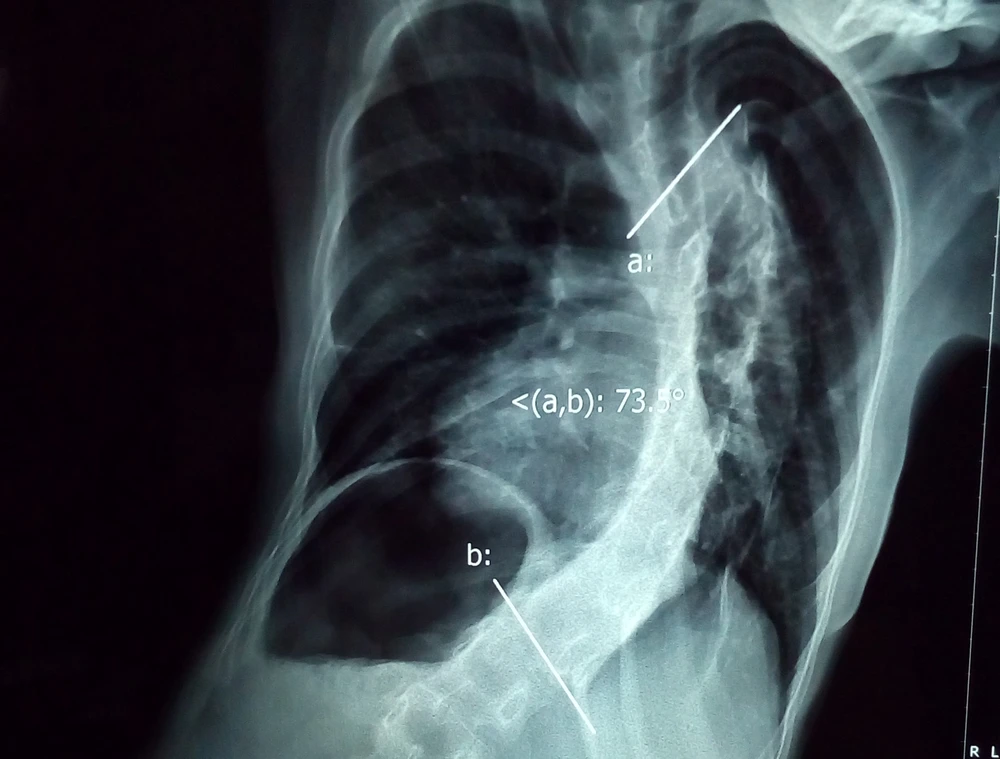

Trước đó, bệnh nhi được đưa vào BV nói trên trong tình trạng đi đứng khó khăn do vẹo cột sống ngực rất nặng. Kết quả chẩn đoán ghi nhận bệnh nhi bị vẹo cột sống ngực 111 độ, gần giống hình chữ S. Chưa hết, bệnh nhi còn bị rỗng tủy cổ nên gia tăng nguy cơ liệt trong quá trình phẫu thuật.

Cột sống bệnh nhi cong hình chữ S. Ảnh: HÒA KHÁNH